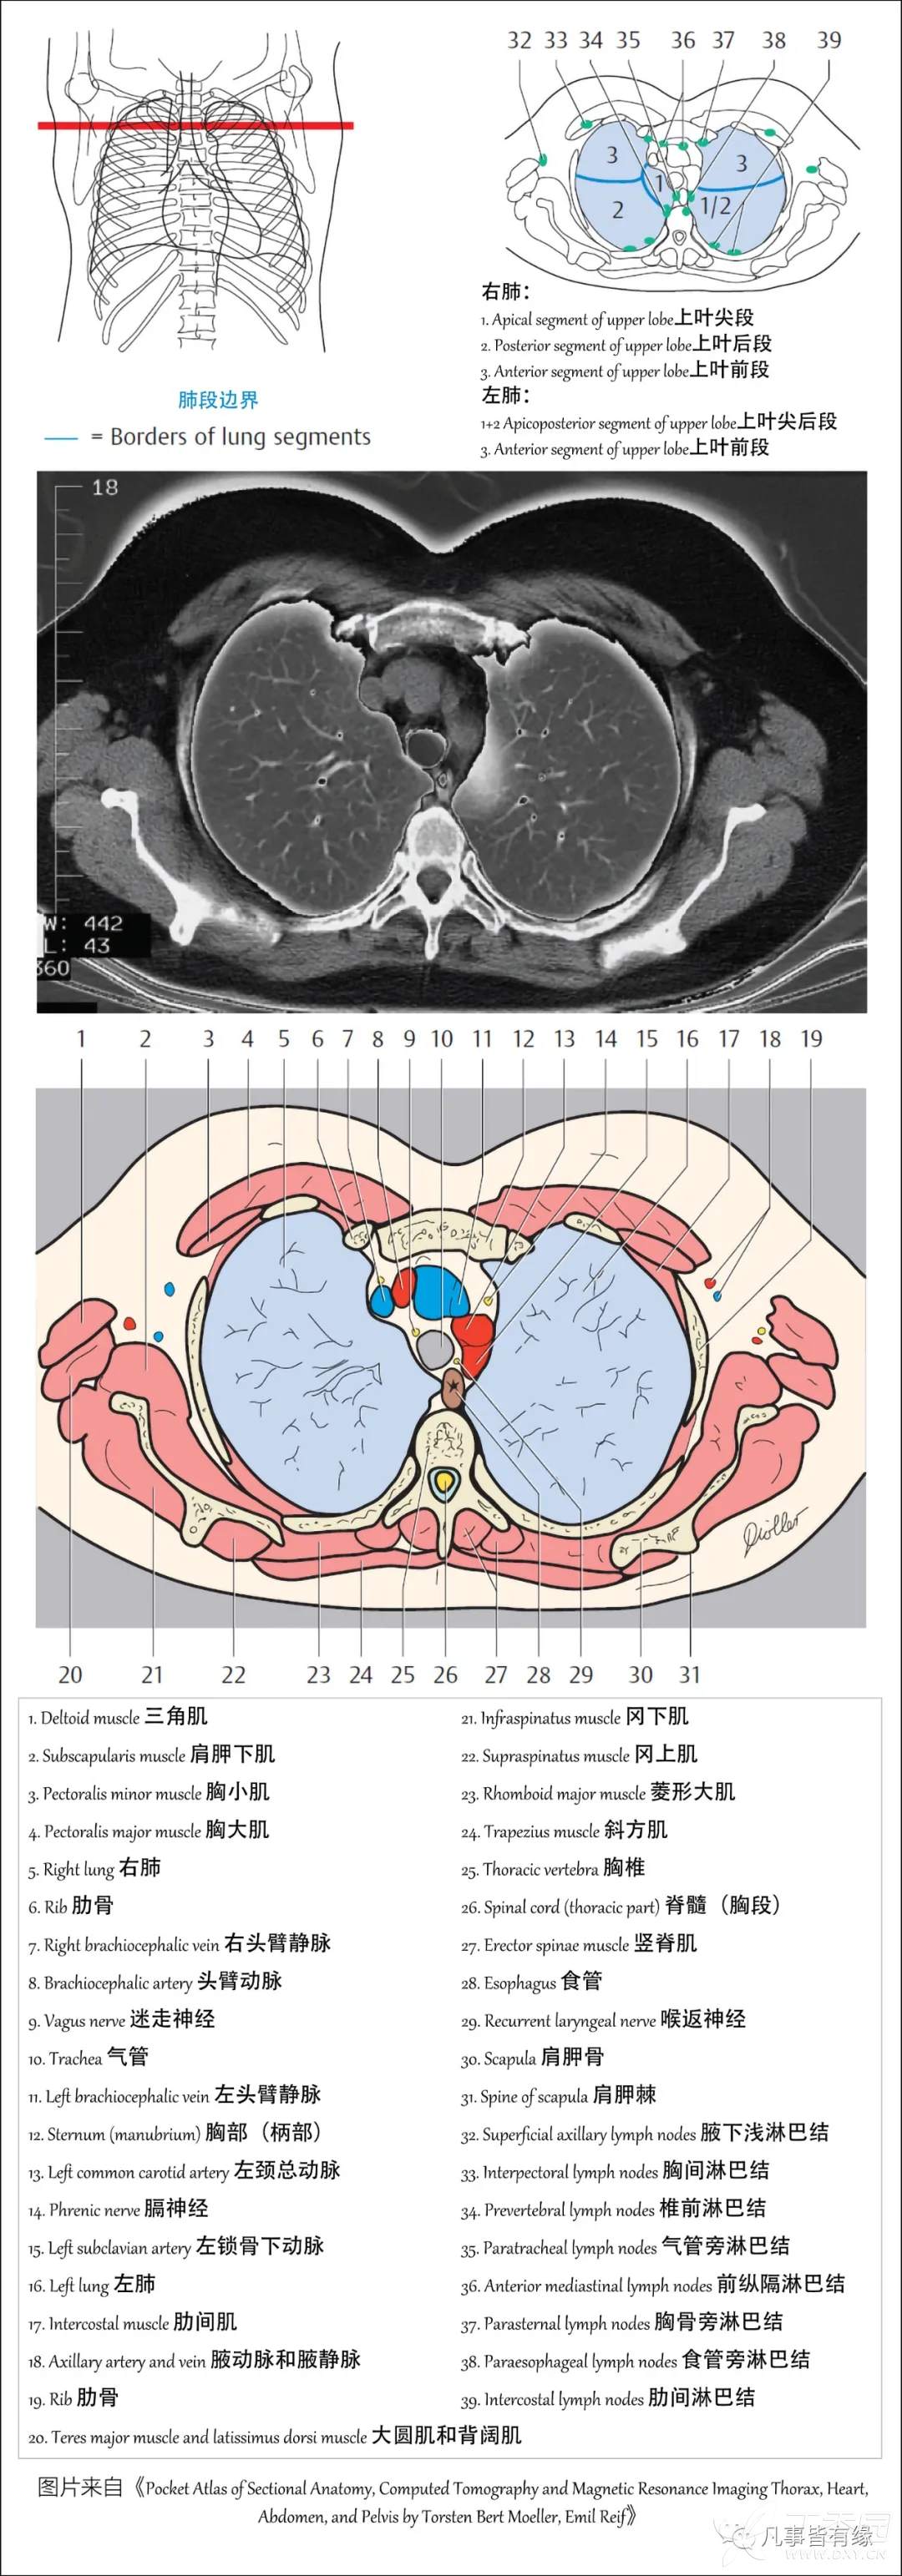

(一)胸部CT轴位断层解剖:

右肺(RightLung)

1.Apical segment of upper lobe 上叶尖段

2.Posterior segment of upper lobe 上叶后段

3.Anterior segment of upper lobe 上叶前段

左肺(LeftLung)

1+2Apicoposterior segment of upper lobe 上叶尖后段